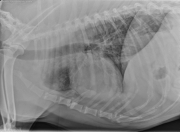

R LAT Thorax

There is a diffuse bronchointerstitial pattern throughout the lungs. The bronchial walls are asymmetrically thickened and visible well out into the periphery. The bronchi do not taper well which may indicate bronchiectasis. Multiple lobar bronchi are visualized with thickened walls. The end-on bronchi form donuts, or cygnet rings. There is also a focus of increased interstitial pattern at the tip of the bronchus to the right cranial lung lobe. The cardiovascular structures are within normal limits.

• Bronchointerstitial pattern – eosinophilic bronchopneumonia (PIE), parasitic pneumonia, less likely neoplasia.

• Interstitial pattern right cranial lobe – focal pneumonia or fibrosis

• Poorly tapering bronchi – possible bronchiectasis